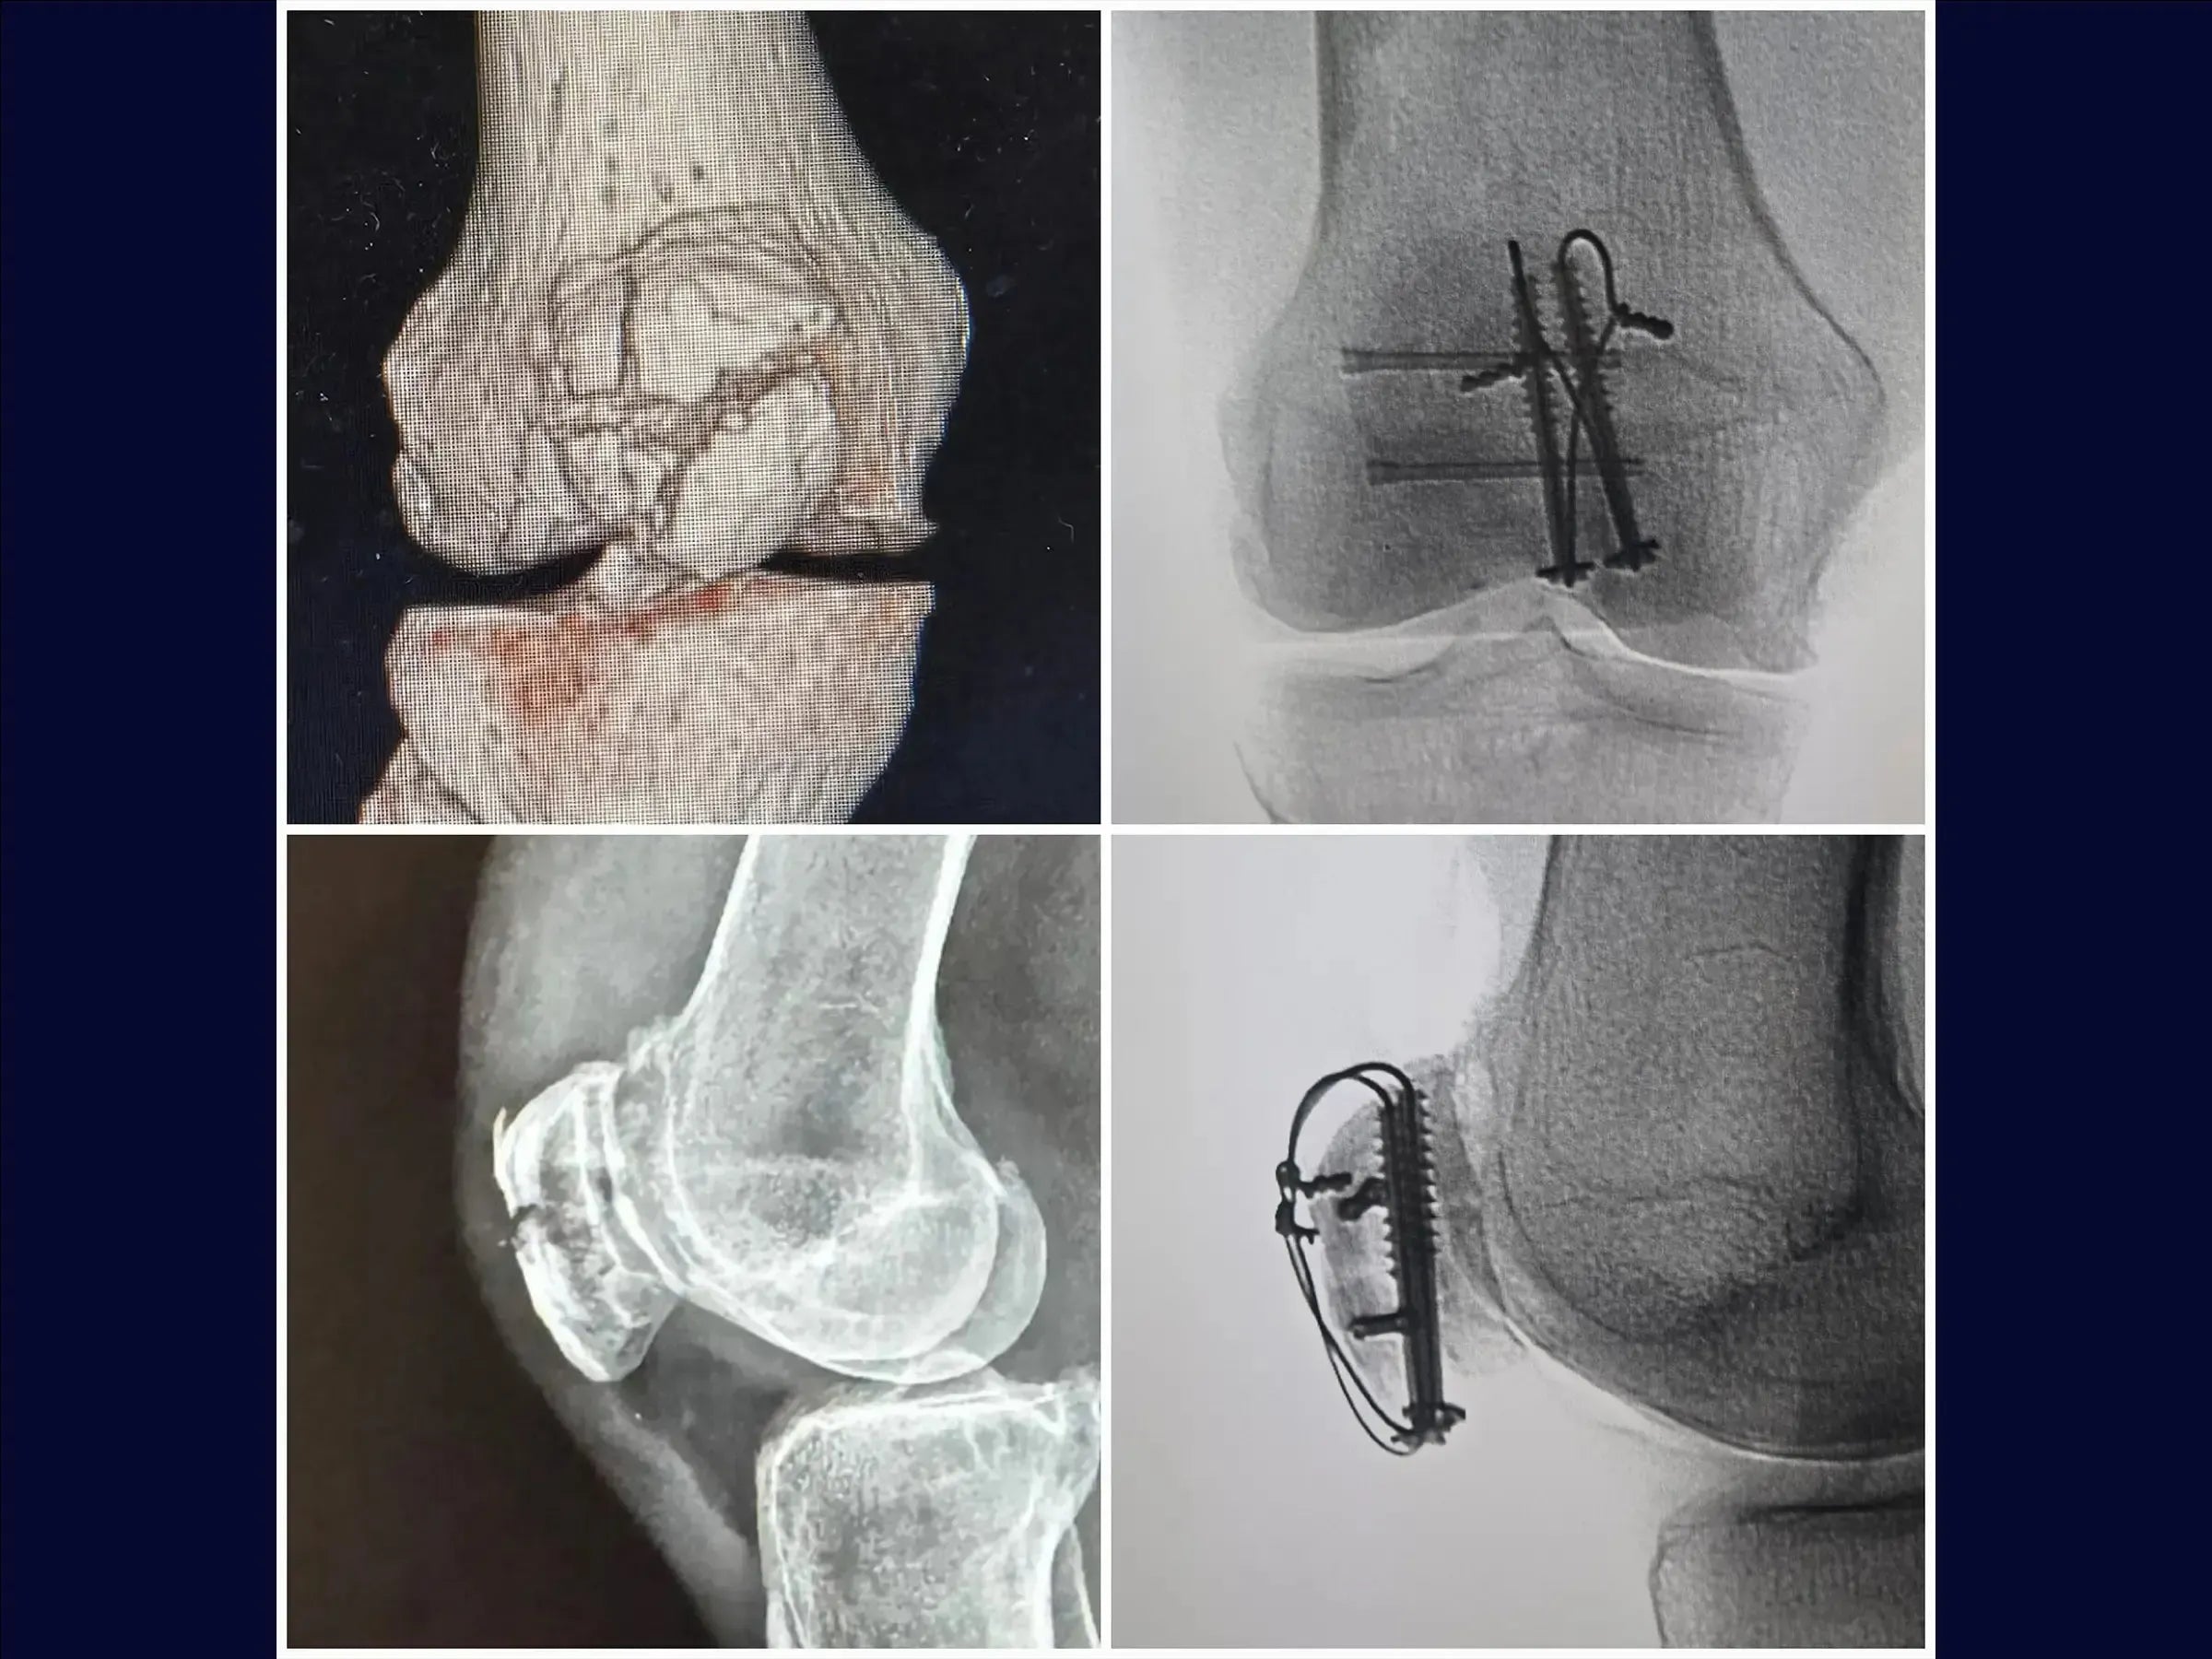

- Uso de parafusos canulados e cerclagem.

- Acesso Cirúrgico Otimizado: Demarcação precisa e incisão única para manipular fragmentos intraoperatoriamente e identificar "dentes" da fratura, facilitando a redução.

- Técnica de Redução Precisa: Metodologia para utilizar a pinça de redução e a mão como molde, ajustando a ancoragem para estabilidade primária sem translação.

- Aplicação de Cerclagem Eficaz: Confecção de incisões longitudinais no tendão quadricipital para posicionamento justo do fio ao osso, com técnica de tração e sepultamento das pontas na massa muscular para evitar complicações.

- Fixação de Fragmentos Laterais: Utilização de parafusos de dupla compressão para fixação de fragmentos na aleta lateral, com sepultamento completo da cabeça para prevenir proeminência do implante.

- Identificação do Fragmento Chave: Foco na importância do polo inferior inserido ao tendão patelar como ponto crucial para a redução e concentração de parafusos com arruela para estabilização.